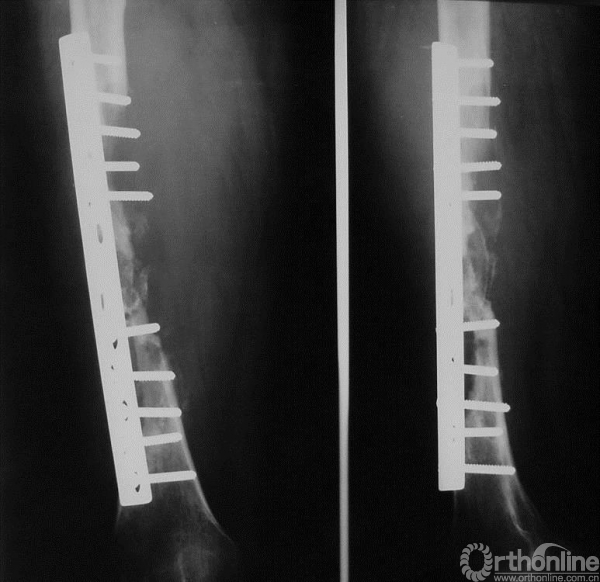

图15-5 第二次术后X线平片正侧位

二次术前考虑一次手术时内固定方式仅为普通的髓内针,强度不足,且填充的骨水泥影响骨折愈合;此次未见明确局部复发,因此行髓内针及骨水泥取出、取髂骨植骨、钢板内固定术